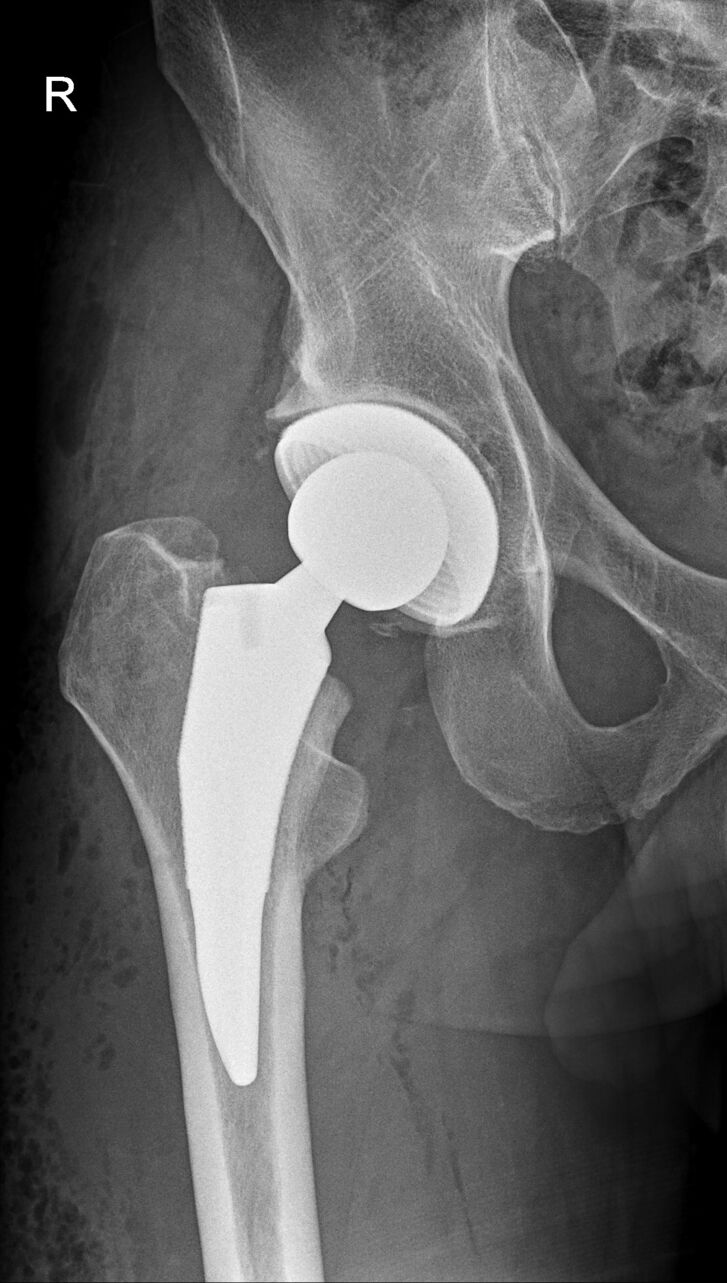

Nach diesen sechs Wochen steht ein Kontrolltermin samt Röntgen an: „Sofern dann alles in Ordnung ist, braucht es keine weiteren Therapien mehr und Herr Jochum kann nach eigenem Ermessen die Belastung steigern“, erklärt Dr. Johannes Abel. Bei einem normalen Verlauf kann der Arzt dann seinem Patienten alle Belastungen in der Arbeit und im Sport erlauben - trotz des künstlichen Gelenks. „Ich weise die Patienten aber auch immer darauf hin, dass es durchaus Sportarten gibt, die schonender für das Implantat sind als andere…“